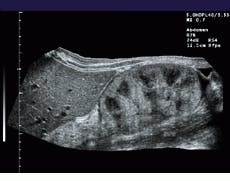

For every new image acquired, its translational and rotational displacements from the previously acquired images are determined. The next acquired image is assumed to have similar features to the previous images, but translated and rotated. Each block in the previous images is compared with the new image. An algorithm, dubbed the XFOV, determines where in the new image each block in the previous image matches best, according to a selected matching criterion, and calculates a relative motion of each block from the previous image to its best matching point in the new image (see Fig. 2). This motion occurs during the time between acquiring the previous image and the new image. The translations computed for each block in the previous images are called motion vectors.

FIGURE 2. To register images, a computational estimate of local motion between successive images is performed. Fuzzy logic simplifies the analysis of the motion of sucessive images using prior-motion history data. This makes the final motion estimation very stable, even when high amounts of image noise are present.